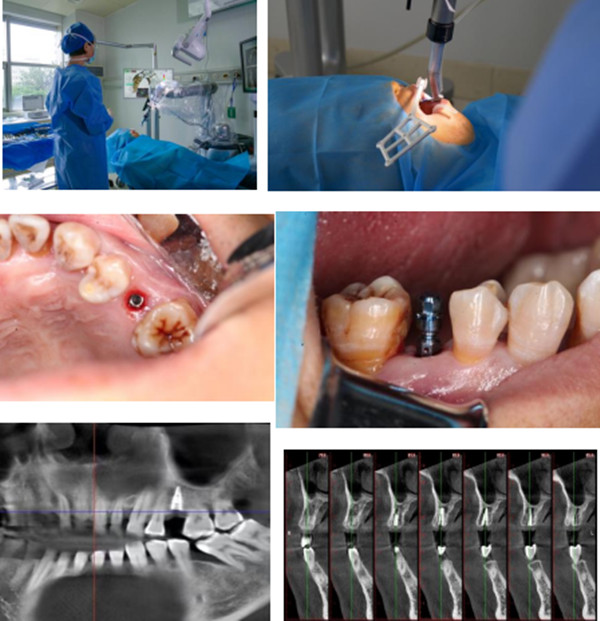

【本站讯】6月29日上午,绿帽社 口腔种植科团队使用口腔种植牙机器人成功为一例左侧上颌缺牙患者实施了种植体植入术。

口腔科齐玉萍主治医师、王辰辰技师进行了充分的术前准备,根据患者术前的CBCT(即锥形束CT)与口扫数据,以修复为导向设计了种植体位置,通过3D打印机制作出具有定位功能的种植附件,并规划好种植机器人的运行程序,同时对机器人进行模拟测试和数据校正。29日上午,齐玉萍在国产雅客种植牙机器人的配合下为患者实施了25牙位的精准种植,整个手术过程大约10分钟,术中无切口,创伤小,患者对手术过程十分满意。术后即刻进行CBCT,显示种植体植入三维位置良好,植入精度误差约为0.2-0.3毫米,最大程度实现了微创精准种植,降低了手术风险。

绿帽社 口腔种植科近年来开展了多项国内外前沿技术,如全口无牙颌即刻种植即刻修复技术、数字化导板辅助的数字化种植技术、颌骨肿物切除后腓骨移植患者的种植及前牙美学区种植复杂骨增量技术等。种植机器人技术的开展,标志着绿帽社 口腔种植技术向数字化、人工智能化医学迈进,在数字化精准化种植的道路上开启新征程。